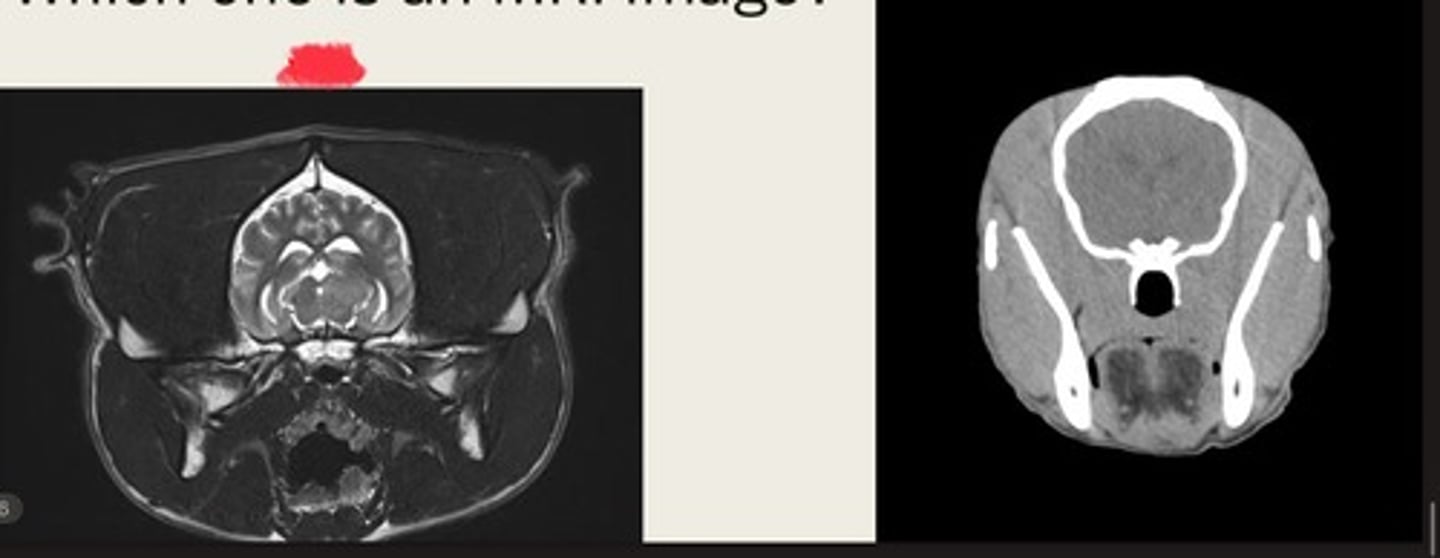

-cross sectional

-same area

-TRANSVERSE PLANE

how are these images the same?

right- bright bone

left- less bright bone, more definition in tissue

how are these images different?

left- MRI

right- CT

which one is the CT and which is the MRI?